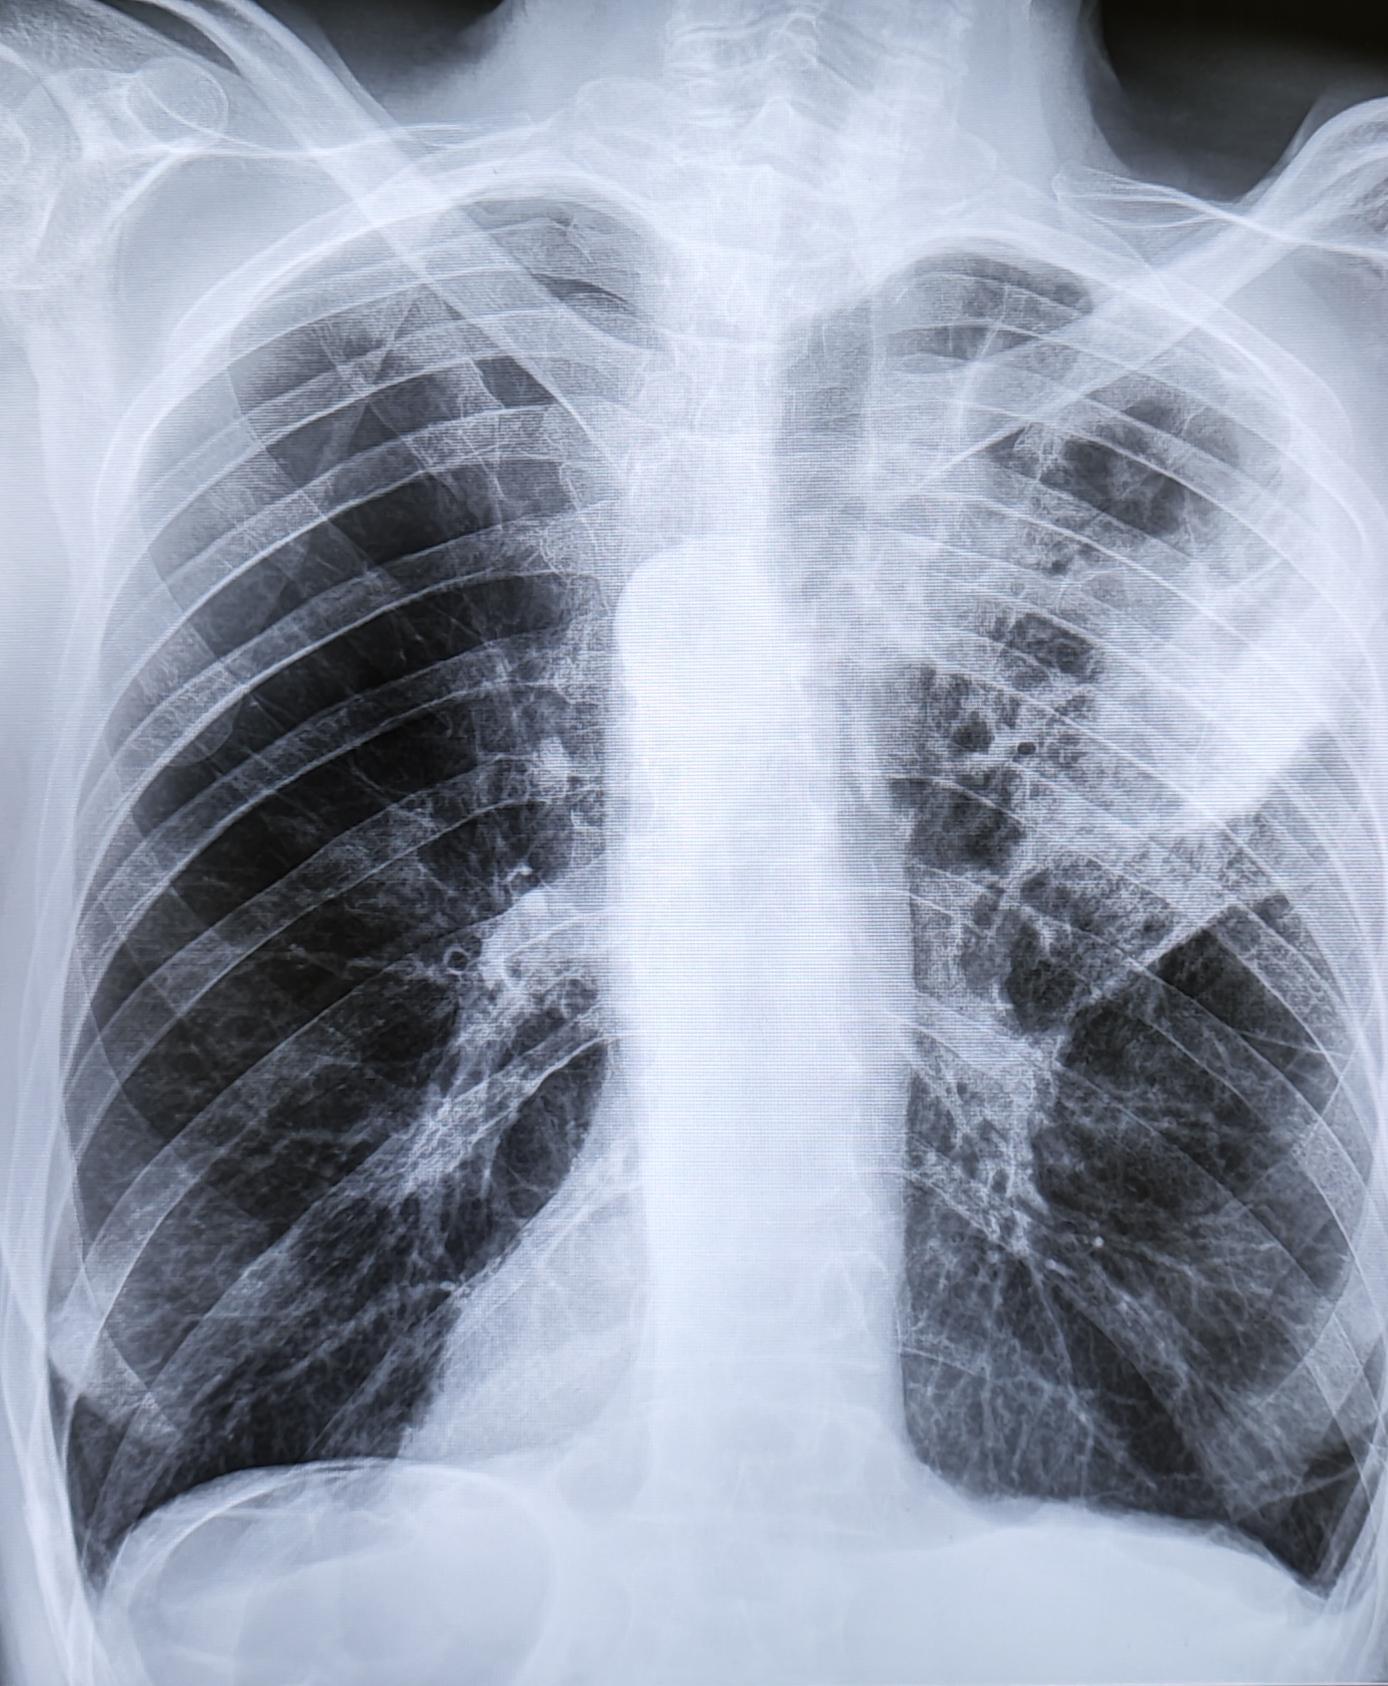

Внебольничная пневмония-рентген

Жалобы на слабость, одышку, не продуктивный кашель ,повышение температуры тела до 38.8 град.

На Р-граммах ОГК в 3х проекциях: На фоне сниженной пневматизации, визуализируются инфильтративные изменения легочной ткани в S2, S3 правого легкого. Легочный рисунок усилен за счет сосудистого компонента. Корень слева-не увеличен, справа-увеличен. Диафрагма не изменена, контуры ее ровные, четкие. Тень сердца обычного расположения не расширена в поперечном размере. Дуга аорты склерозирована. Дегенеративно-дистрофические изменения грудного отдела позвоночника.

Заключение: Правосторонняя бисегментарная S2, S3 пневмония.

Рек: конс.пульм./тер. Р-контроль через 12 дн. после лечения.

Данный диагноз соответствует ст.53-Временные функциональные расстройства органов дыхания после острого заболевания, обострения хронического заболевания, травмы или хирургического лечения- Г-временно не годен к военной службе сроком 1-3 мес. в зависимости от решения терапевта ВВК.